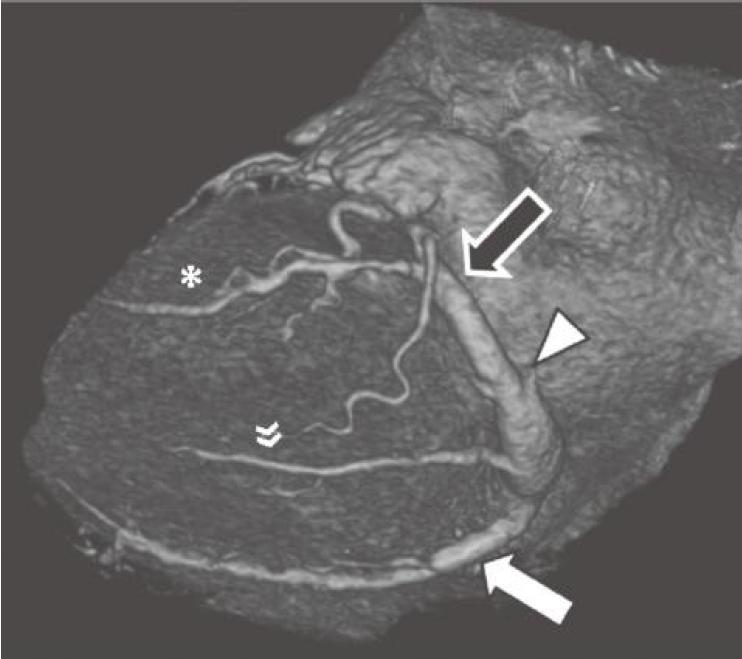

图13-4 RCA优势型,RCA绕过右心缘,在RAVG的下方发出后降支(箭),并走行于后室间沟(虚线)。心中静脉(箭头)也在后室间沟内走行

RCA.右冠状动脉;RV.右心室;LV.左心室

当冠状动脉为RCA优势型时,RCA可走行至RAVG的下部,并发出走行于后室间沟的后降支。在约50%的RCA优势型人群中,还有一条明显的后外侧支,沿LAVG的下半部分走行,供应左心室下外侧壁心肌。这一分支还可能为二尖瓣的下间隔乳头肌供血,因此对其进行准确识别尤为重要。